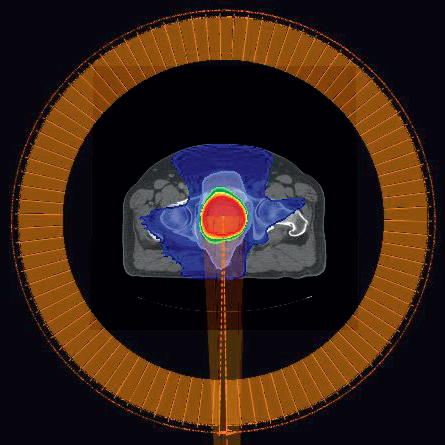

Figure 2

Figure 2: CDR plan for prostate patient P1. For the CDR plan, the MU per gantry angle is constnant. The total MU is 465 MU (5.19 MU/cp) and the delivery time is 93 seconds.